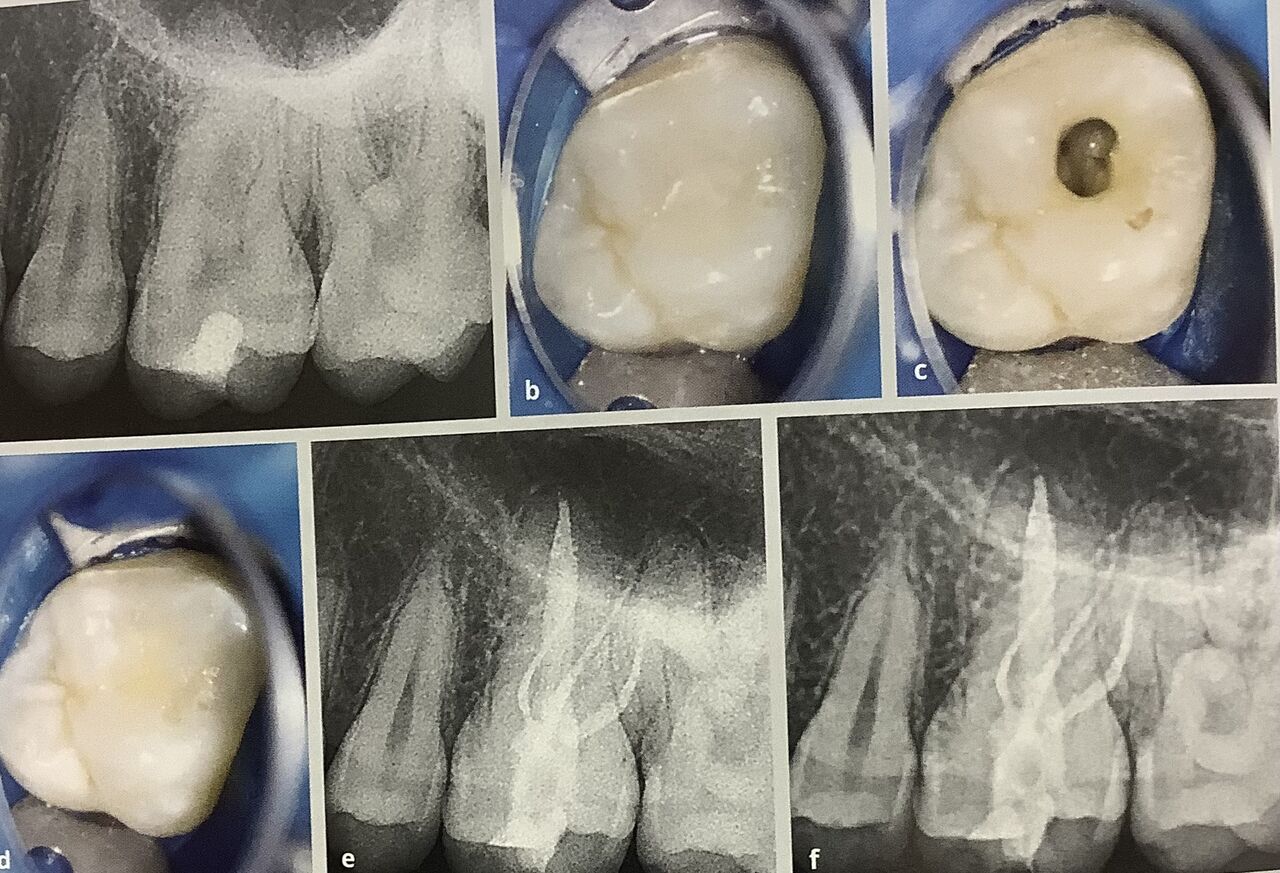

根管治療では神経へ器具が通る道、アクセスの穴を真ん中に開ける必要があります。

被せるために全周を削ると、根元部分に残る歯の厚みは本当に少なくなっちゃいます。

しかし根管治療した奥歯では、咬む所を被うべきです。

タガをかけて被って抑えることで、開く力に耐えて折れない様にするためです。

上に乗せるオンレイ、4分の3だけ被う被せ物、あるいは全部被せる方法があります。

セラミックよりも金の被せ物の方が削る量は少なく済みます。